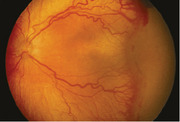

Retinopathy of prematurity (ROP) and anemia are often comorbid in preterm and low birth weight infants in the United States. However, the relationship between ROP and anemia in infants is unclear across prospective and retrospective studies due to confounding from other comorbidities of prematurity and variable study designs. Molecular mechanisms that may underlie this association include tissue hypoxia, oxidative stress, inflammation, and the timing of onset of anemia relative to the phase of ROP. Furthermore, maternal or neonatal disruptions in iron homeostasis, leading to either iron deficiency or accumulation, have been associated with ROP. Further studies, including randomized clinical trials, are needed to better elucidate the association between ROP and anemia, as well as the impact of the timing of the onset of anemia.

Abstract Image